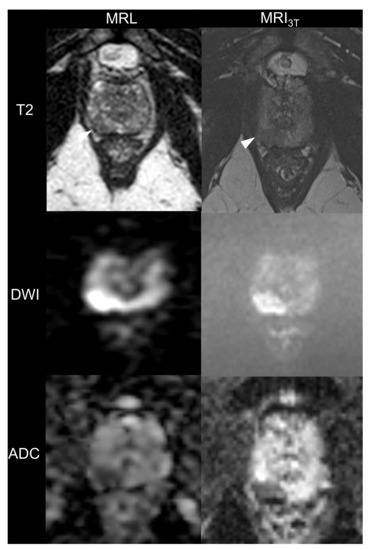

3.1.1. Image Quality

3.1.2. Lesion Conspicuity and Diagnostic Confidence on MRL Alone and in Consensus with MRI3T